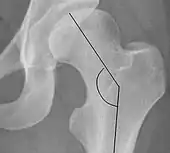

| Cervical diaphyseal angle | ![]() |

The angle formed between the femoral neck and femoral diaphysis | 120° to 140°